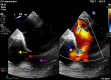

We present a case of a 56-year-old patient with obstructive sleep apnoea (OSA) presenting with acute decompensated heart failure and signs of cardiogenic shock. Echocardiography and CT imaging led to the diagnosis of acute type A aortic dissection (AD) complicated by aortopulmonary fistula (APF). The patient underwent successful surgical repair with complicated postoperative course including pulseless electrical activity arrest. This case highlights the underappreciated role of untreated OSA as a risk factor for AD. Furthermore, it presents an opportunity to review APFs as a rare complication of AD. We discuss the available evidence linking OSA and AD, review currently reported cases of APF, briefly outline the haemodynamics of this acute left-to-right shunt and discuss management of this rare but deadly complication.